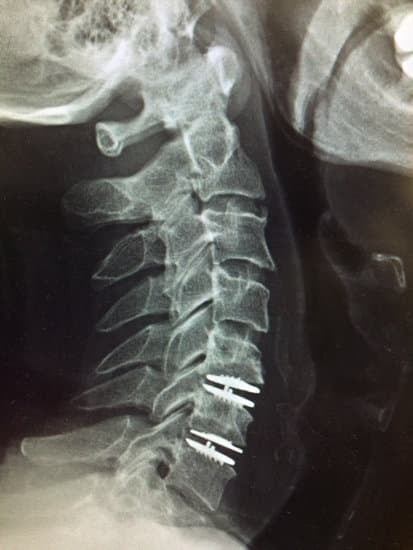

인공 디스크 치환술(ADR)은 손상된 경추 디스크(추간판)를 제거한 후, 이를 대신해 인공 디스크를 삽입하는 수술입니다.

인공 디스크 삽입

제거된 디스크 자리에 금속과 고분자 소재로 만들어진 인공 디스크를 삽입합니다.

이 인공 디스크는 척추의 움직임을 유지하면서 신경이 눌리지 않도록 설계되었습니다.

수술 후 몇 개월 동안 X-ray 및 기타 검사를 통해 인공 디스크 상태를 확인합니다.